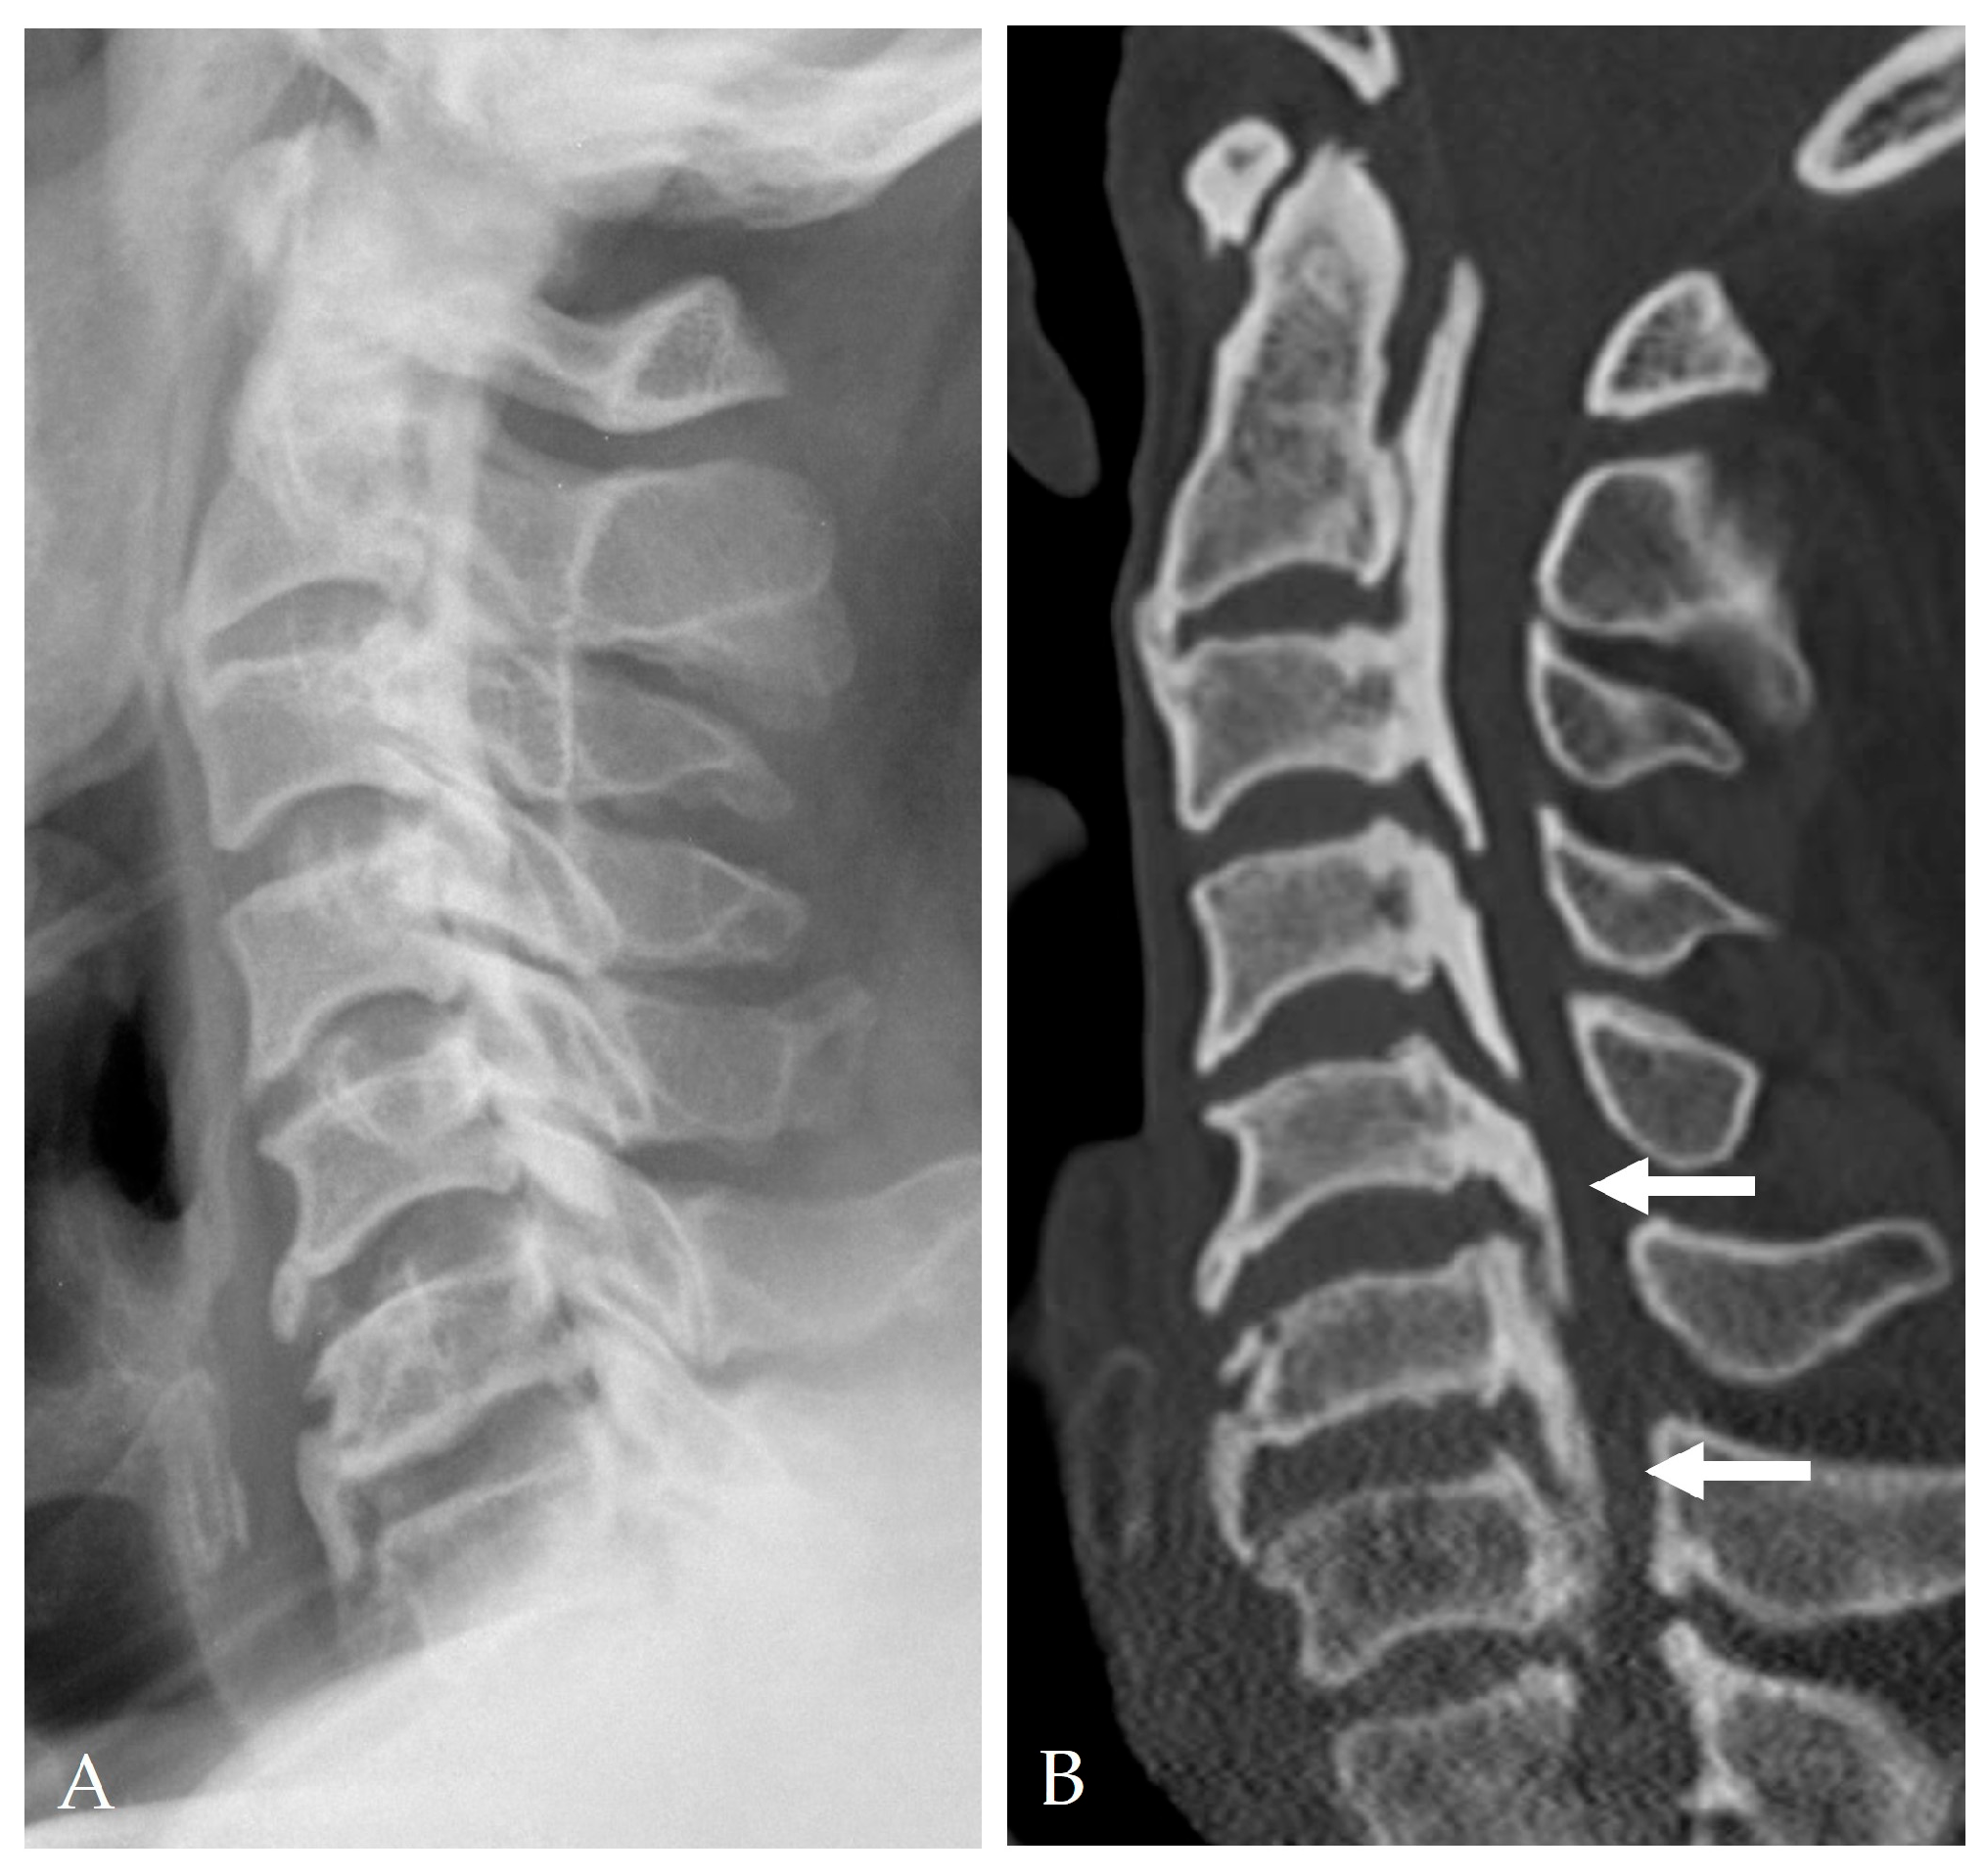

2.4. Radiologic Predictors and Morphological Correlates

- Broad-based or continuous/mixed-type OPLL: Confers approximately 10-fold higher risk of DT than segmental types [37].

2.5. Disease-Specific Factors: Dural Ossification and Adhesion Severity